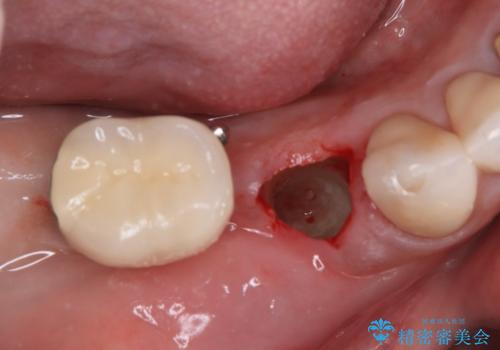

そのため、当院に新しく導入した手法により、抜歯をした日にインプラントを埋入し、そのままを仮歯を装着することで、他の歯への負担を軽減する計画を立てました。

インプラント埋入時に植立具合の安定性を測定したところ、十分な数値が得られたため、速やかに仮歯を装着して咬合回復をさせることができました。

抜歯を含めた外科処置を1回に抑えることができ、あっという間に治療を終えることができました。